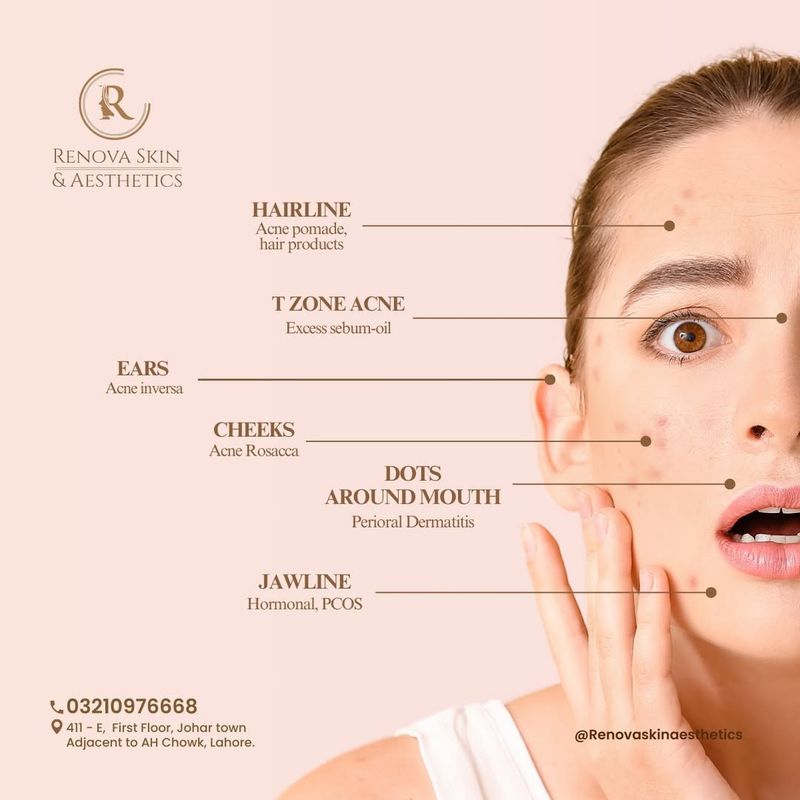

6. Acne Breakouts

Carb-heavy meals can sometimes lead to unexpected breakouts, as high-glycemic foods cause blood sugar spikes that contribute to skin inflammation.

Swapping refined carbs for whole grains and adding more omega-3-rich foods can help support clearer skin, minimizing breakouts while enhancing your natural glow.